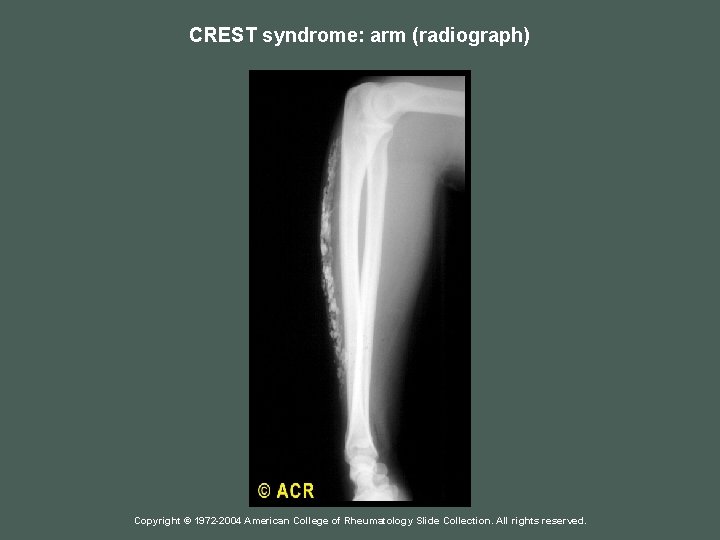

CREST syndrome: arm (radiograph) Copyright © 1972 -2004 American College of Rheumatology Slide Collection. All rights reserved.